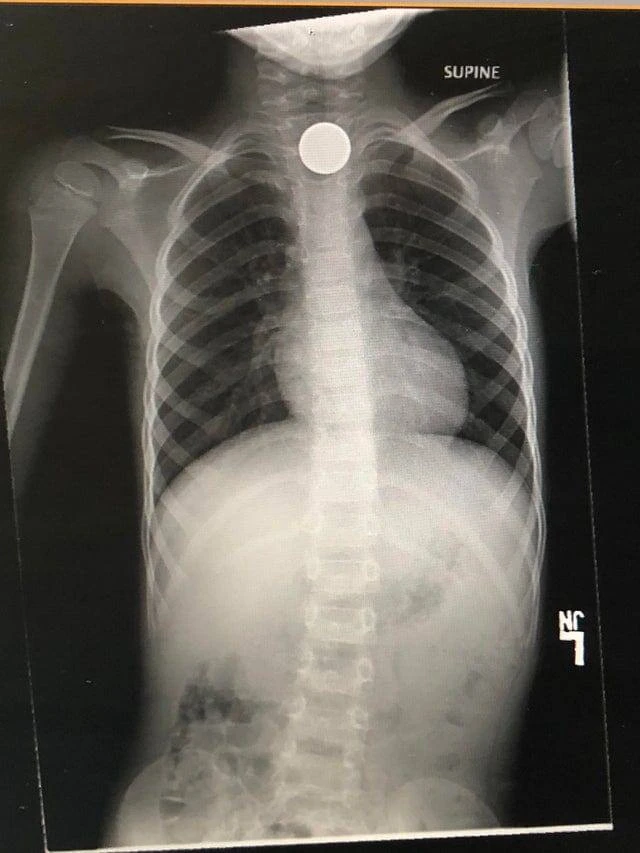

2. Мій син вирішив проковтнути монетку і перетворив її на величезний рахунок від лікаря